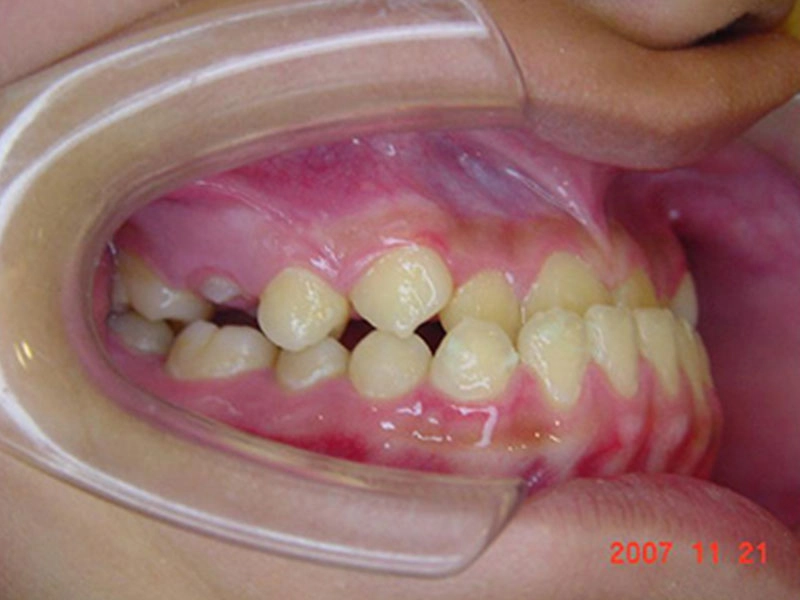

矯正前 (11 歲 5 個月)

戽斗矯正案例-4